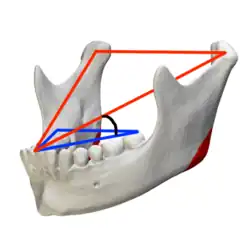

Bei einer Totalprothese entfällt diese Funktion. Eine alleinige Front- und Eckzahnführung würde ein Aushebeln und Kippen der Prothesen bewirken. In Ausnahmefällen kann sie als Grundlage dienen, beispielsweise bei ausgeprägtem Kieferkamm und jungen Prothesenträgern.[3] Aus diesem Grund werden Prothesenzähne so aufgestellt und entsprechend eingeschliffen, dass keine aushebelnden Führungszonen bestehen. Vielmehr werden absichtlich Balancekontakte hergestellt. Dies bedeutet, dass bei einer Seitwärtsbewegung des Unterkiefers – im Gegensatz zur natürlichen Vollbezahnung – die Zähne beider Seiten unter Kontakt aufeinander gleiten. Bei der Vorschubbewegung des Unterkiefers gleiten neben den Frontzähnen auch die Molaren der Ober- und Unterkieferprothese übereinander und sorgen für eine distale (hintere) Abstützung.[4] Hierzu werden die Zähne gemäß der Spee-Kurve (sagittale Kompensationskurve) aufgestellt.[5]

Die Wilson-Kurve hat ihre Bedeutung beim Aufstellen der künstlichen Zähne in der Kalottenartikulation von Totalprothesen.[6] Die Seitenzähne einer Unterkieferprothese werden – von der Kaufläche her – gegen eine kalottenförmig gewölbte Schablone aufgestellt und bilden eine transversale Kompensationskurve. Hierdurch wird später in Funktion (beim Kauen) eine beidseitige „balancierte“ Okklusion erzielt. Die Wölbung der Kalotte ist von der Höckerneigung der Prothesenzähne und der Kondylenbahnneigung abhängig. Die Kondylenbahnneigung ist die Neigung der Gelenkbahn gegen die Campersche Ebene oder Frankfurter Horizontale (s. u.). Die Anwendung der Wilson-Kurve hat in der Kalottentheorie von George S. Monson (1920) ihren Ursprung. Danach treffen sich die Zahnachsen aller Oberkieferzähne in einem gemeinsamen Punkt, der im Bereich des Hahnenkamms (lateinisch Crista galli) des Siebbeins (lateinisch Os ethmoidale) liegt. Die Kauflächen liegen auf der gekrümmten Oberfläche eines Kugelausschnitts mit einem Durchmesser von 28,8 cm.[7]

Speesche Kurve (sagittale Kompensationskurve)

Speesche Kurve (sagittale Kompensationskurve) -

Wilson-Kurve (transversale Kompensationskurve)

Wilson-Kurve (transversale Kompensationskurve)